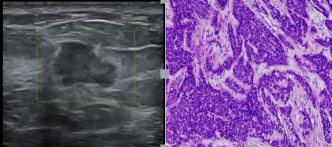

超声作为乳腺检查的首选,那如何检查出乳腺癌呢?超声通过观察病灶的边界、形态、内部回声、血流以及腋下淋巴结等帮助诊断病灶的良恶性。2002年美国放射学会制定了“乳腺影像报告和数据系统”(Breast Imaging Reporting and Data System),简称为BI-RADS,目的是对钼靶、超声和磁共振乳腺检查报告的结论和格式进行规范化。

超声提示:右侧乳腺结节(BI-RADS 4级),术后病理提示浸润性乳腺癌